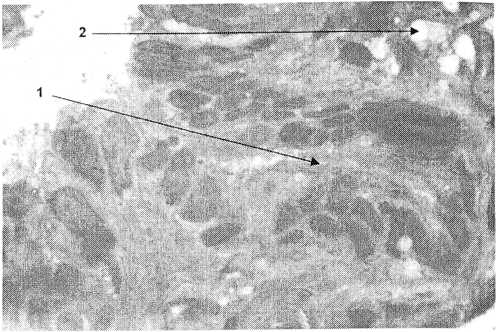

Рис. 2. Гидросальпинкс.

Высота эпителия 13 μт, цилиарный индекс 42%, наблюдается слипание складок слизистой оболочки (1), эпителий деструктивен, много вакуолей в строме (2). Микрофотография эпоксидных полутонких срезов. Окраска: метиленовая синь и основной фуксин, увеличение х400